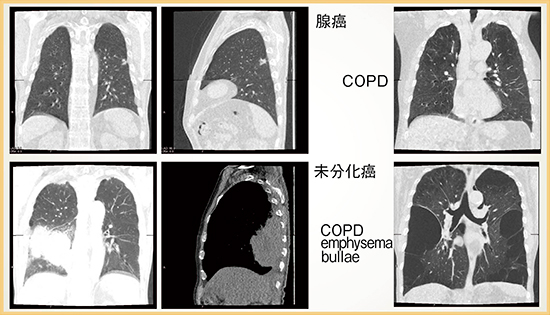

Dynamic Volume Scanを用いた自由呼吸下の胸部CT(呼吸ダイナミックCT)の研究および臨床応用について検討を行った。呼吸ダイナミックCTを用いて肺の動きを見ることで,肺がんの胸壁への癒着の有無が一目瞭然となるため,胸壁浸潤の判定に非常に有用である。実際の診断能は,感度100%,特異度97%,正診率79%と,非常に良好な成績であることが報告されている5)。また,病変と近傍の肋骨の位置関係を数値として評価することで,癒着の有無を客観的にグラフで表示することも可能である6)(図3)。

呼吸ダイナミックCTは,慢性閉塞性肺疾患(COPD)にも応用されている。COPDでは左右の肺が同調せずに動きがいびつとなるため,呼吸相ごとにプロットし,グラフ表示することで評価が可能となる7)。また,COPD患者は,心機能が悪いことが知られている。呼気時に肺から空気が排出されないため心臓が圧排されることが,呼吸ダイナミックCTにて可視化されており8),心機能悪化の原因として新たな知見が示された可能性がある。